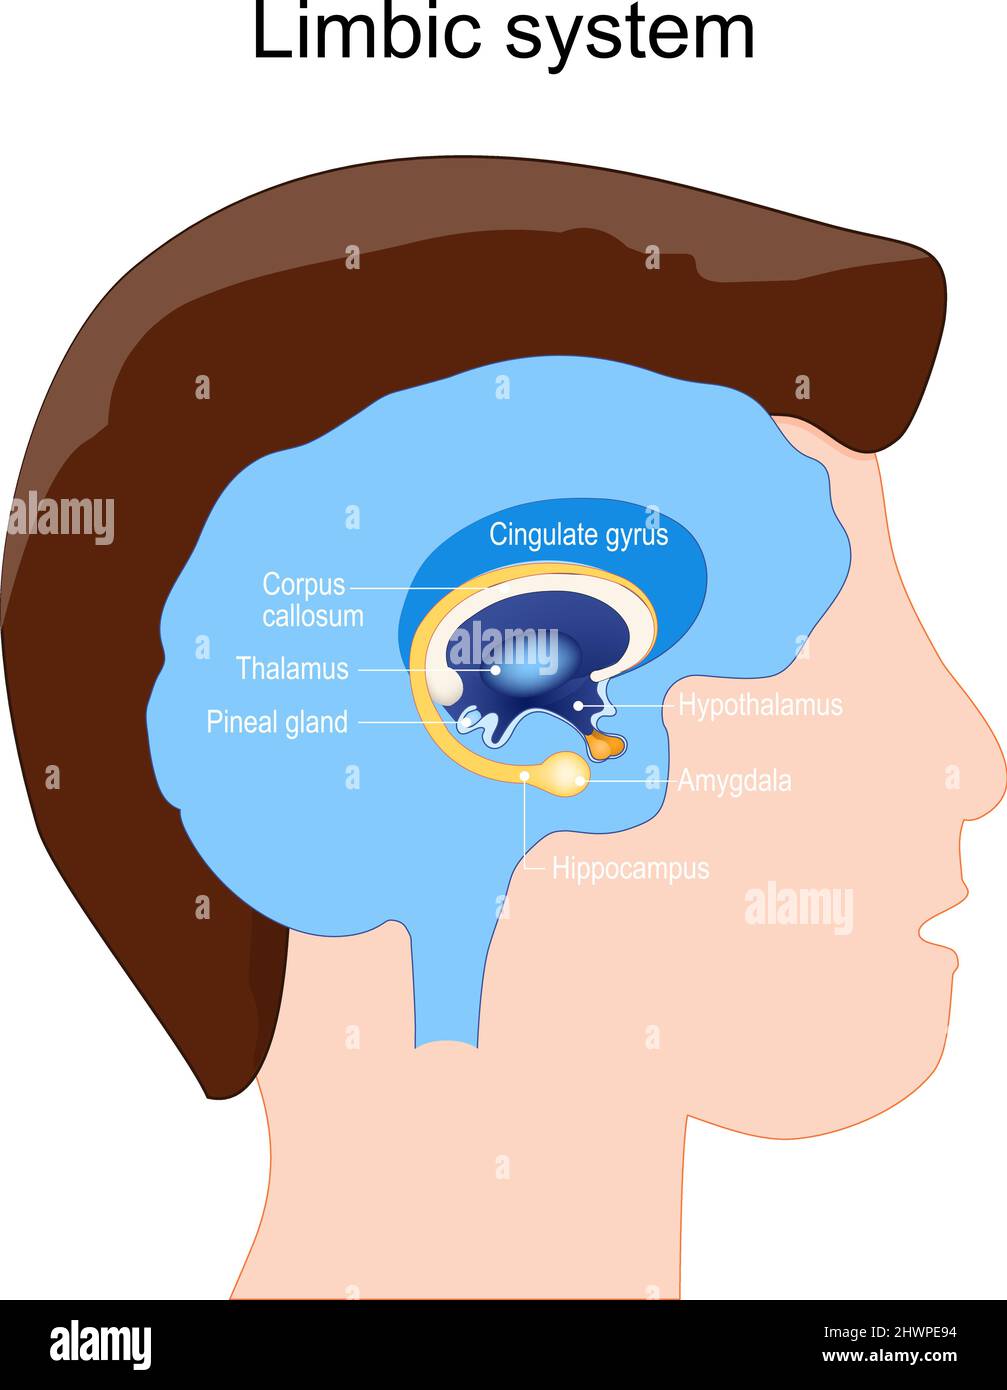

RF2HWPE94–Anatomia del sistema limbico. Struttura dei gangli cerebrali: Amigdala, ghiandola pineale, Thalamus, Ippocampus, Cingulate Giro, Corpo calloso, Ipotalamo.